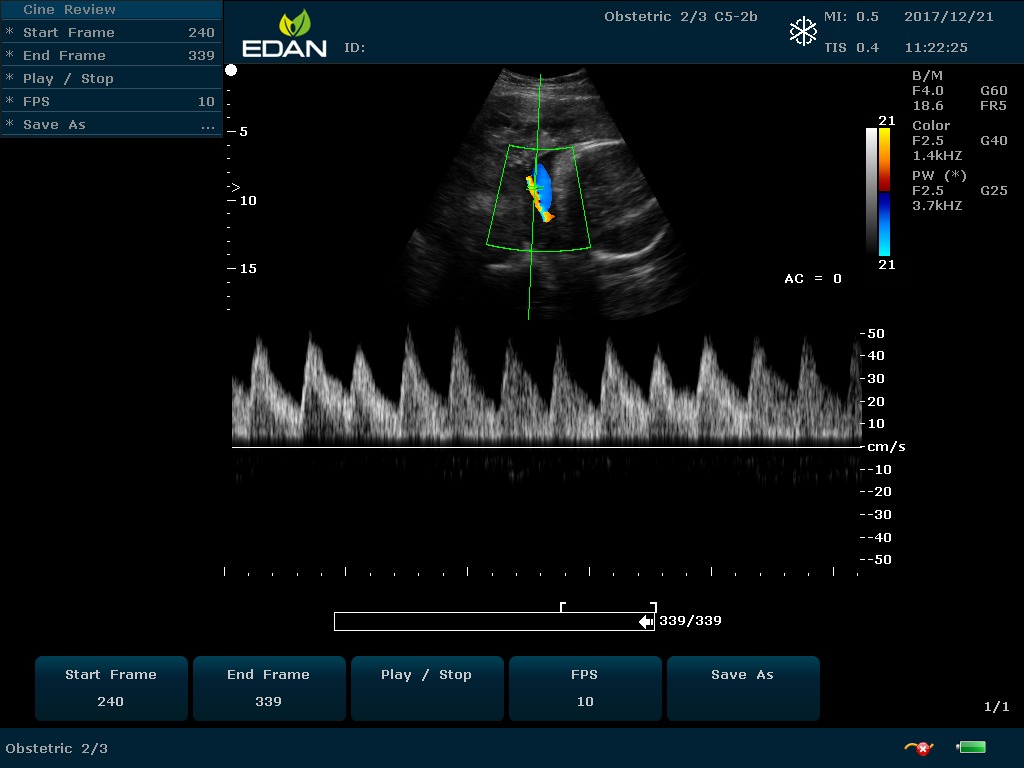

Передовые технологии позволяют повысить качество визуализации в несколько раз. УЗИ-аппарат U60 Edan отличается возможностью быстрой настройки визуализации. Специальные функции позволяют моментально отображать данные за счет быстрой оптимизации параметров. Режимы визуализации: B-mode, M-mode, Color Doppler, Power Doppler Imaging, Pulsed Wave Doppler, Continuous Doppler.

• Цветовое Допплеровское картирование

• Импульсная Допплерография